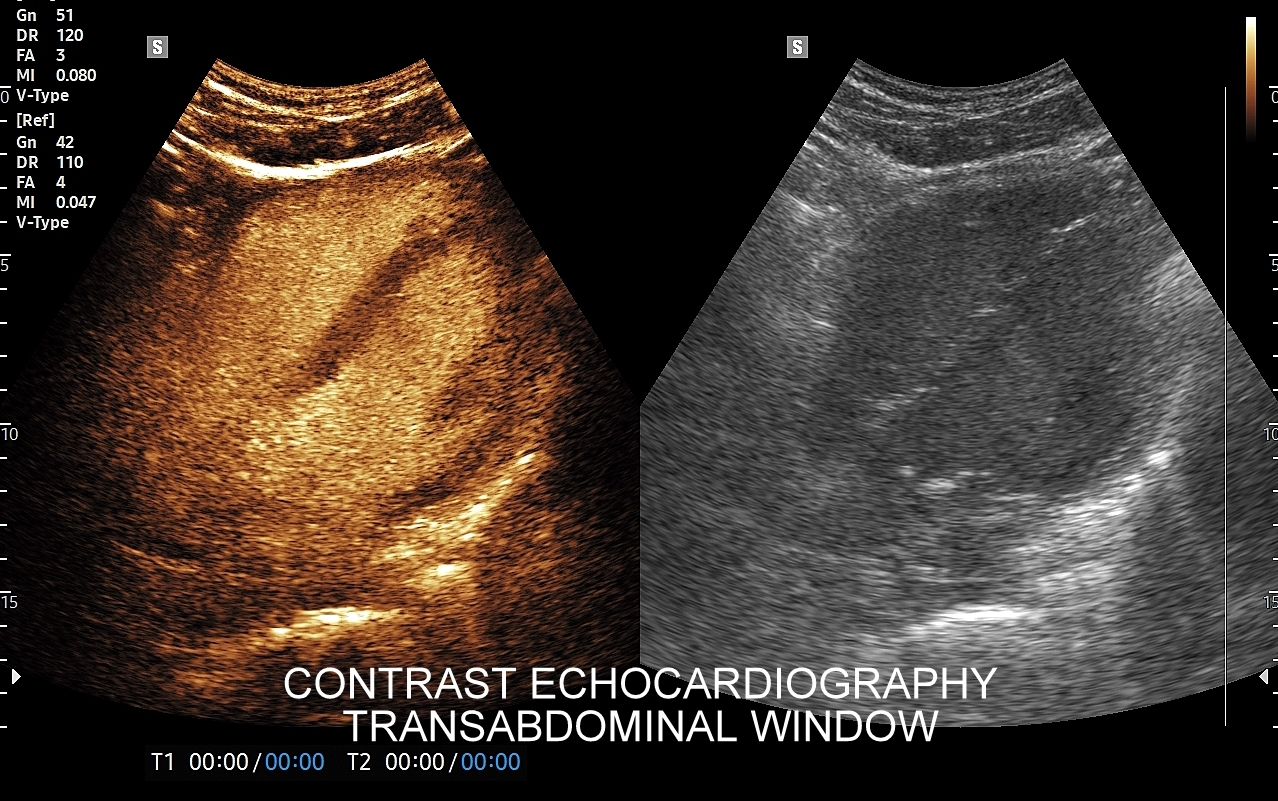

Badanie USG z kontrastem, z języka angielskiego CEUS (contrast enhanced ultrasound), jest badaniem ultrasonograficznym, podczas którego, zwykle dożylnie, podaje się specjalny kontrast w celu uwidocznienia struktur narządowych oraz tkanek, które niewystarczająco wyraźnie są widoczne lub charakteryzowane w klasycznym badaniu USG, a nawet w innych badaniach obrazowych jak tomografia komputerowa (TK) czy rezonans magnetyczny (MRI).

Strukturę kontrastu do USG stanowią mikropęcherzyki o wielkości <10 μm zbudowane z osłonki lipidowej, w której zamknięty jest neutralny gaz heksafluorek siarki (SF6). Mikropęcherzyki po podaniu dożylnym przedostają się mikrokrążenia narządów i są w nich wykrywane za pomocą obrazowania USG specjalnie do tego przystosowanym aparatem. Oprócz dożylnego podawania kontrastu, w przypadku niektórych wskazań, może być on także administrowany dopęcherzowo.

CEUS jest badaniem w czasie rzeczywistym pozostającym pod kontrolą operatora, podczas którego możliwe jest wykonanie próby czynnościowej oraz natychmiastowe powtórzenie całego badania w razie konieczności. Możliwości takich nie dają ani TK ani MRI. Dodatkowo CEUS cechuje się o wiele większą rozdzielczością czasową w porównaniu do wspomnianych metod, co umożliwia uwidocznienie wczesnej fazy tętniczej unaczynienia podejrzanej onkologicznie zmiany ogniskowej w wątrobie i jej lepszą charakterystykę.